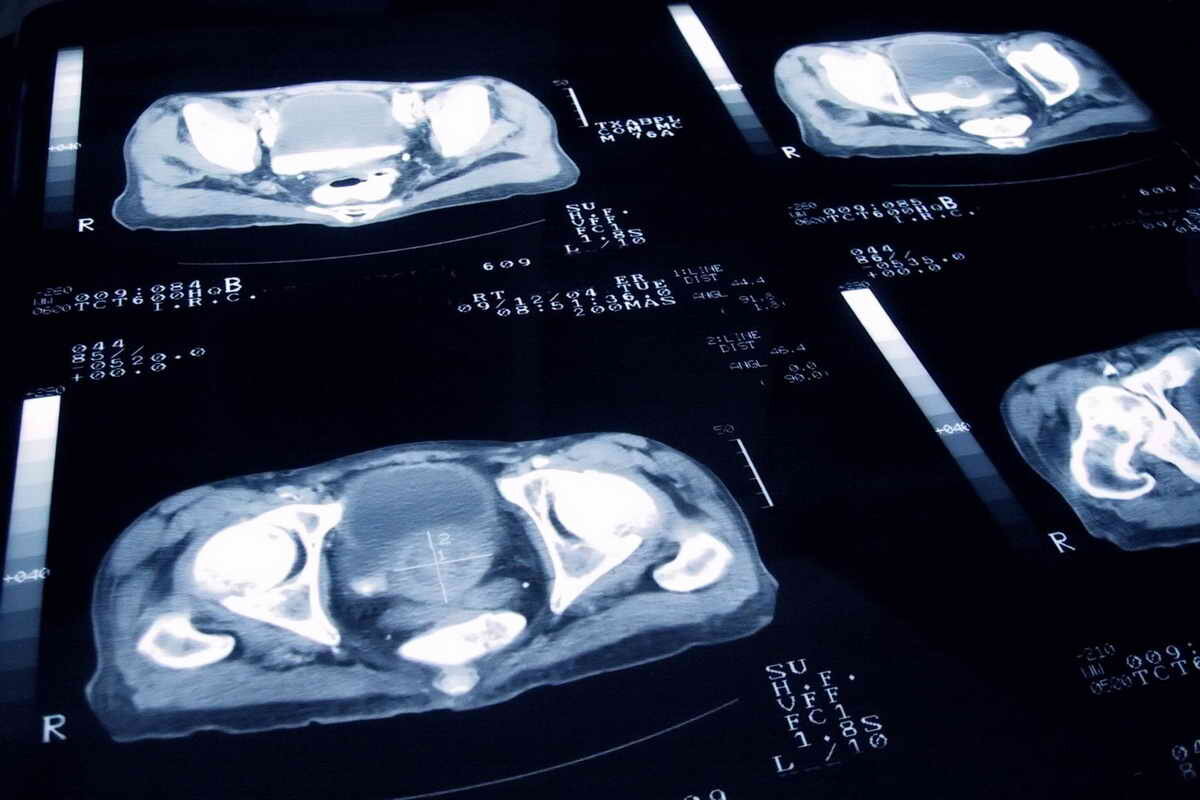

ПСМА-ПЭТ является передовой технологией, которая использует специальные радиотрассеры для точного выявления раковых клеток. В отличие от стандартных методов, таких как МРТ или КТ, эта методика не только отображает анатомические изменения, но и выявляет функциональные признаки активности опухоли. В результате удаётся обнаружить ранее невыявленные метастазы, особенно у пациентов с высокими рисками рецидива.